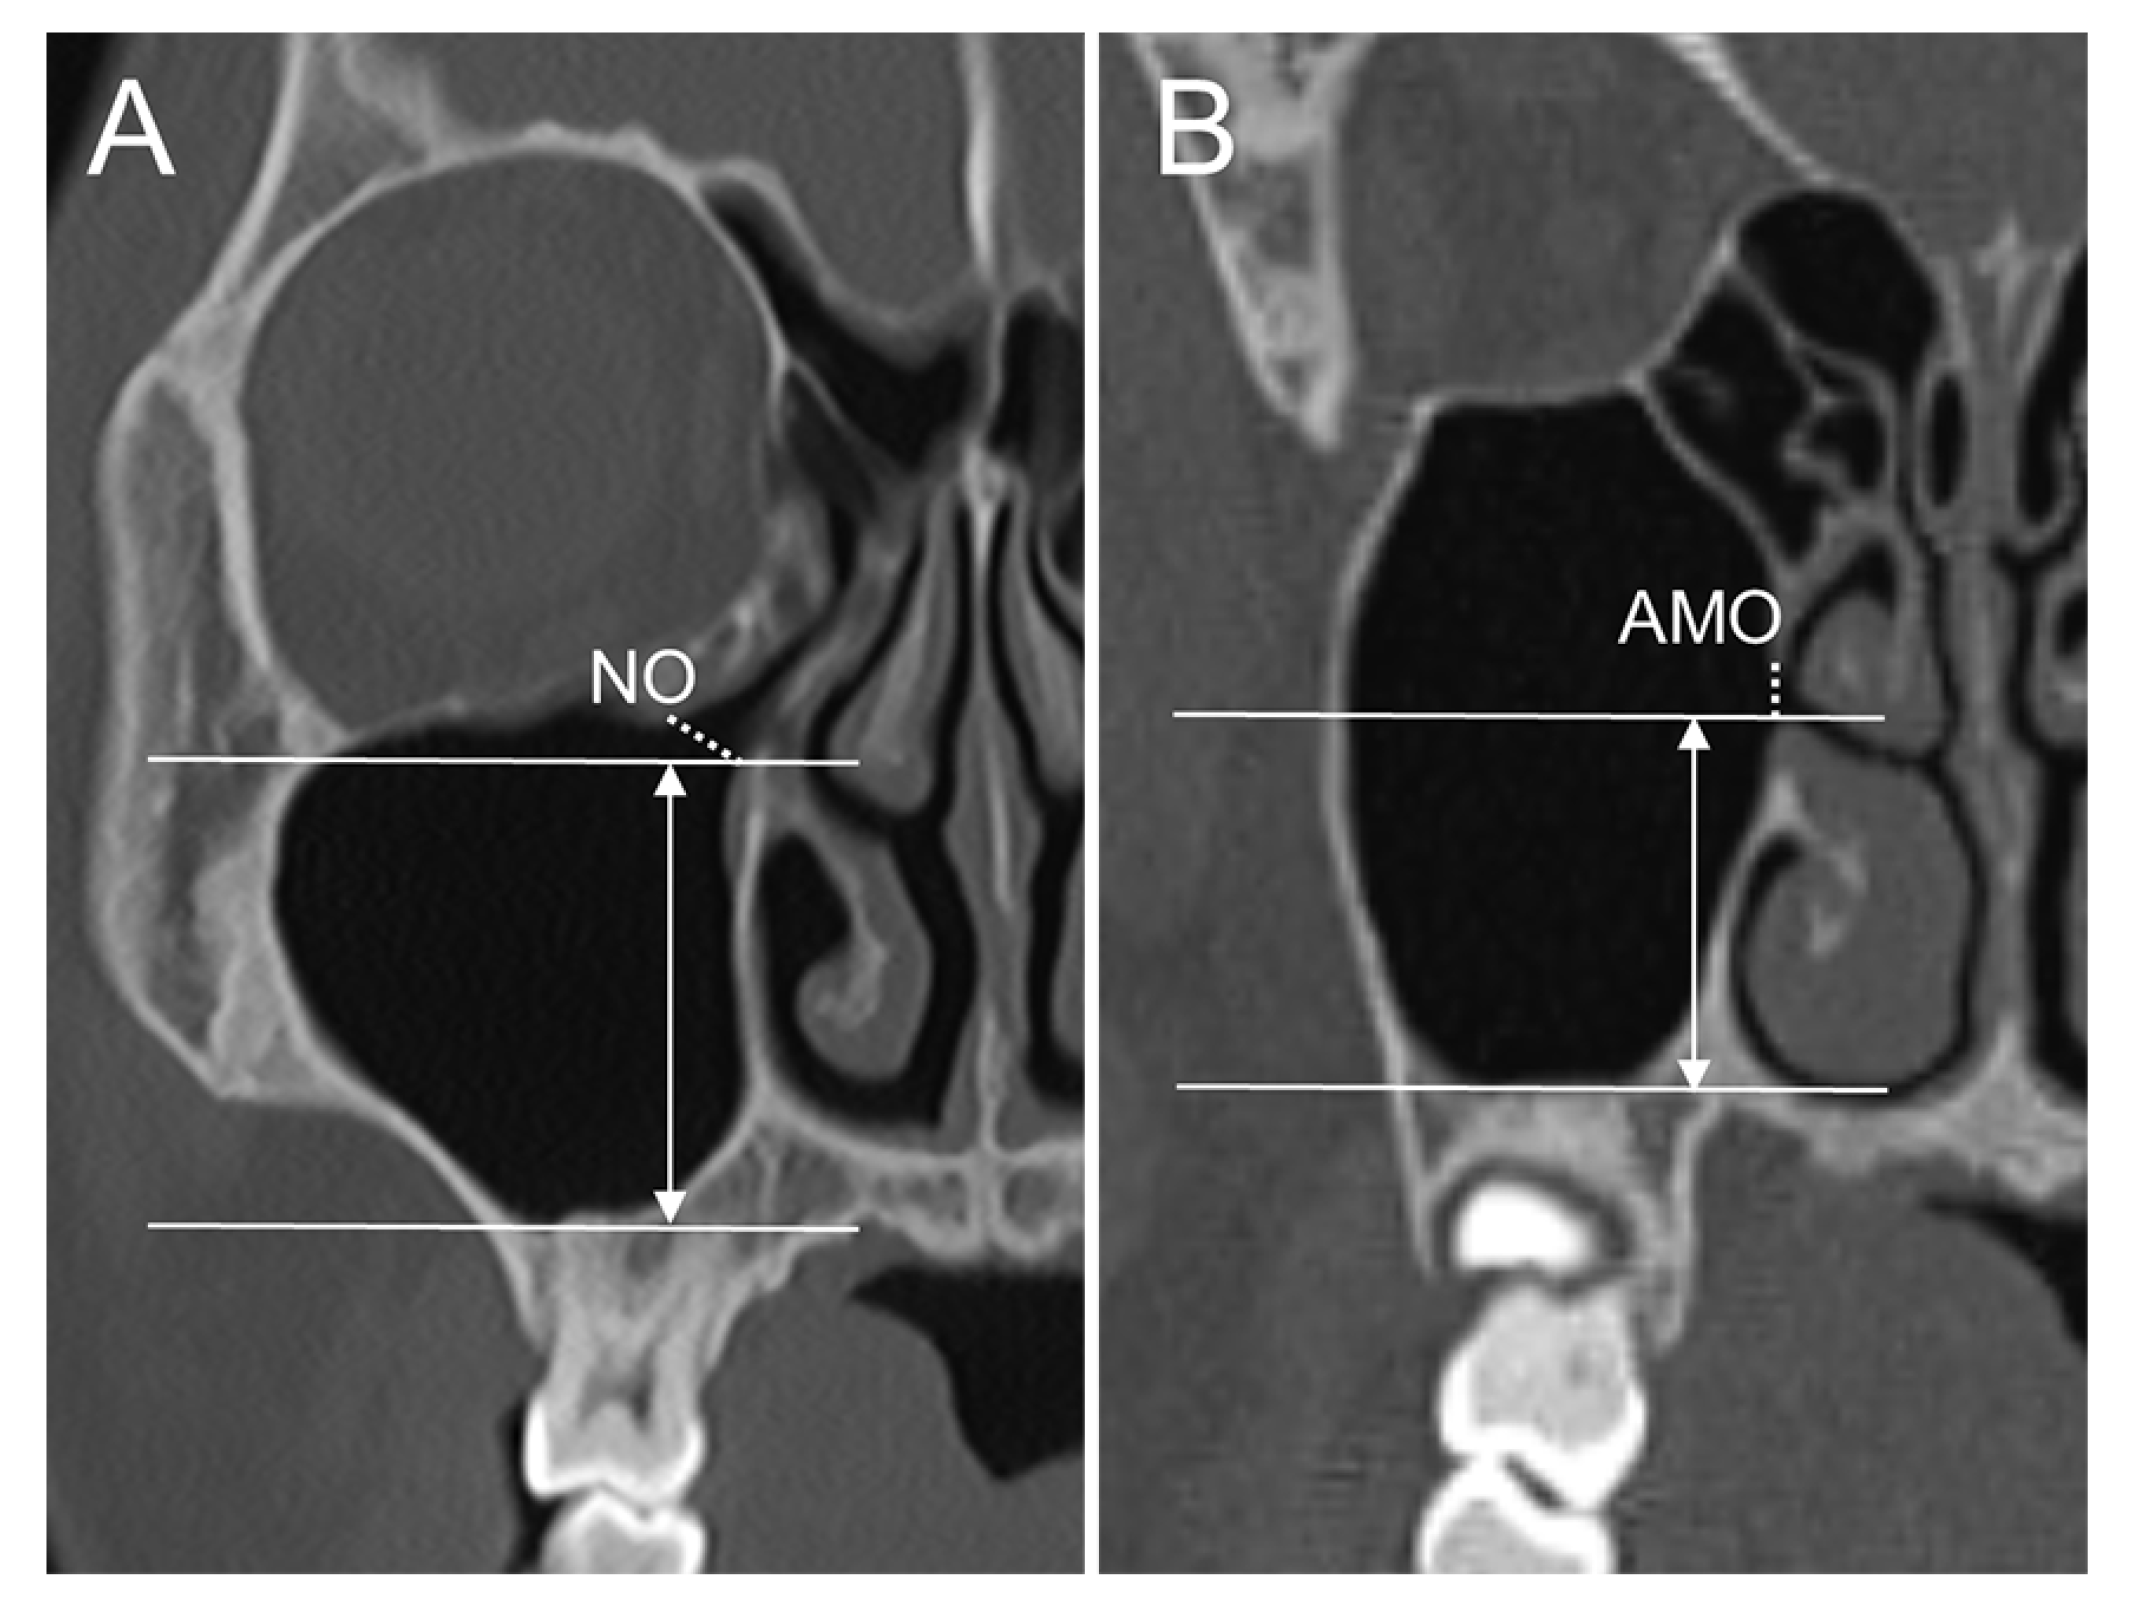

| AMO_SI location_inf | Distance from the MSF to AMO_inf in the supero-inferior direction |

| AMO_SI location_sup | Distance from the OF to AMO_sup in the supero-inferior direction |

| NO_SI location_inf | Distance from the MSF to NO_inf in the supero-inferior direction |

| NO_SI location_sup | Distance from the OF to NO_sup in the supero-inferior direction |